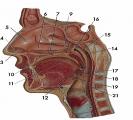

Hard/soft palate

Inferior/middle/superior concha (s.) conchae (pl.)

Nasal Cavity

Nasal septum

Naso/oro/laryngo-phraynx

Oral Cavity

Tongue

Uvula

Vestibule (of nasal cavity)

Vocal folds (=vocal cords)